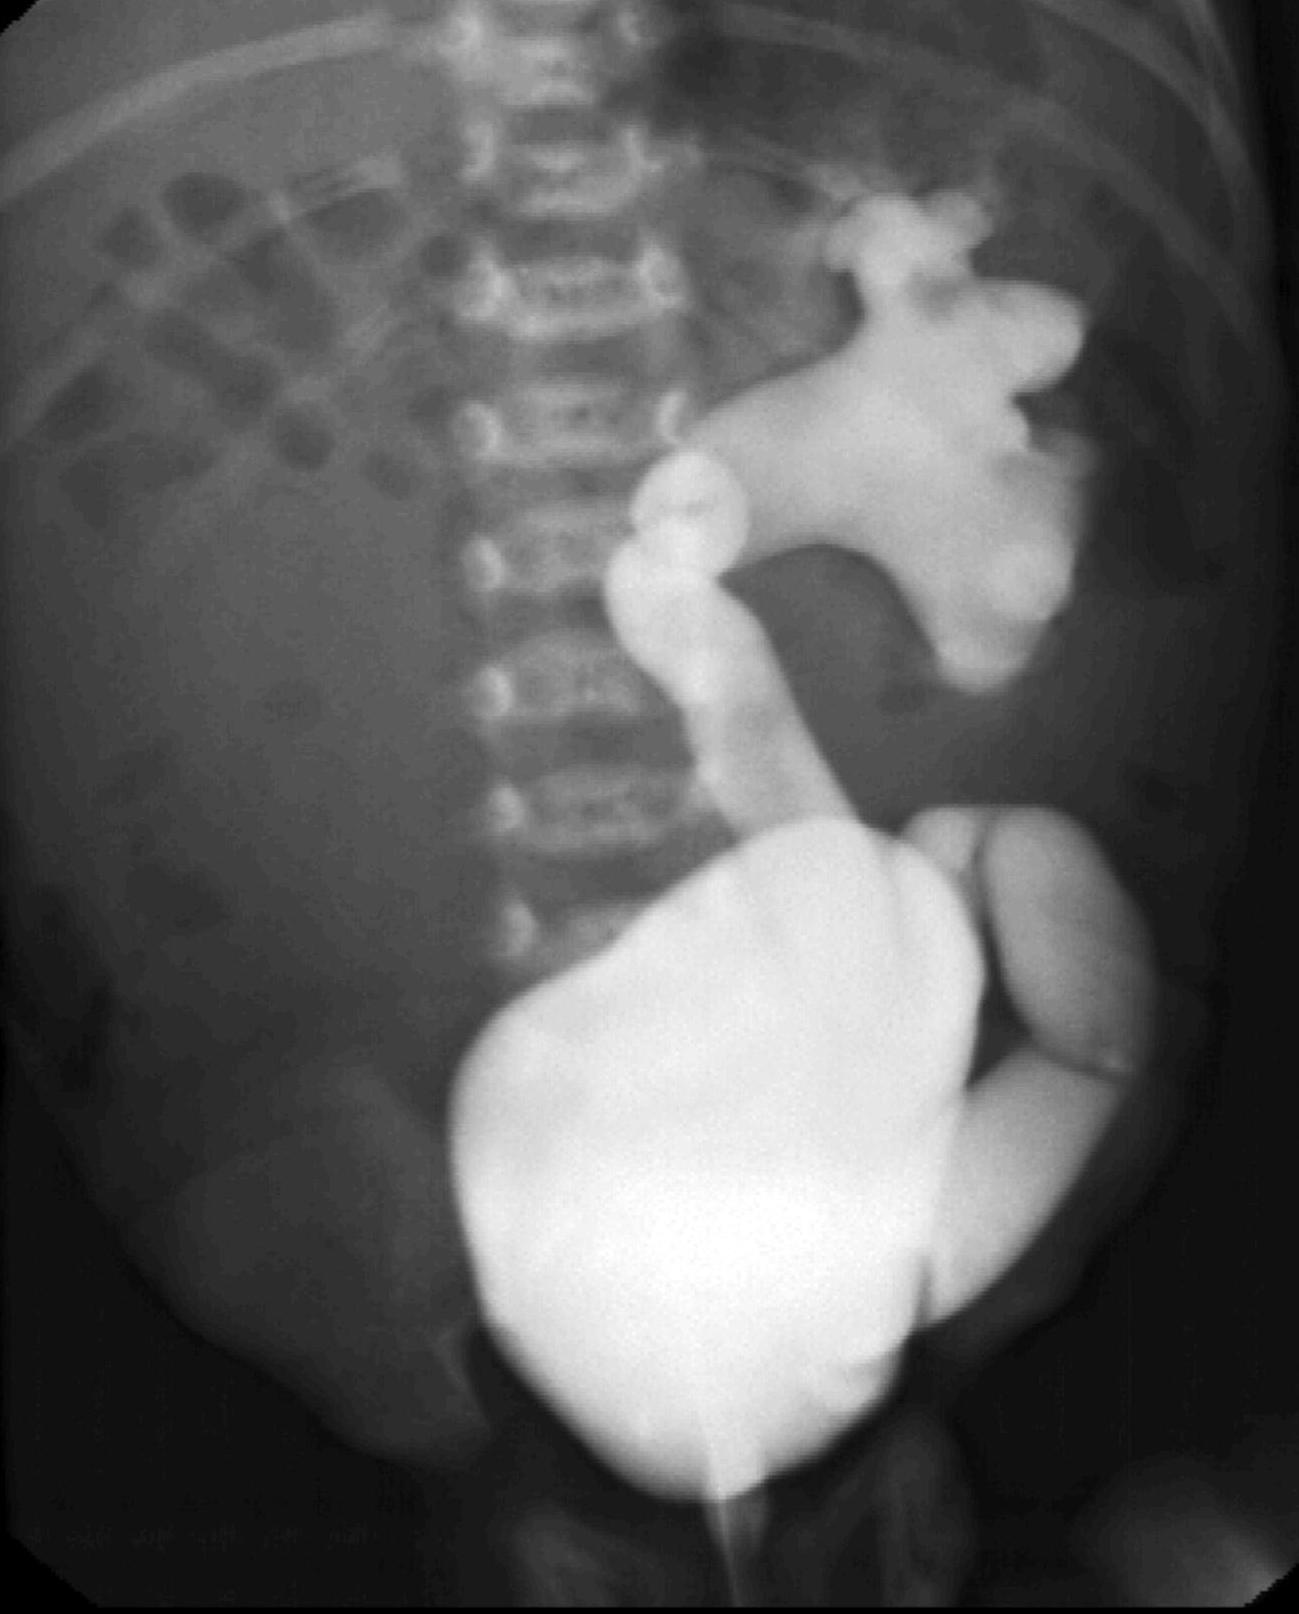

Image

22.The calices and the pyelon of the kidney are markedly dilated, the parenchyma is thinner. Severe hydronephrosis. The ureter is not visible. Pyelouretral stenosis.